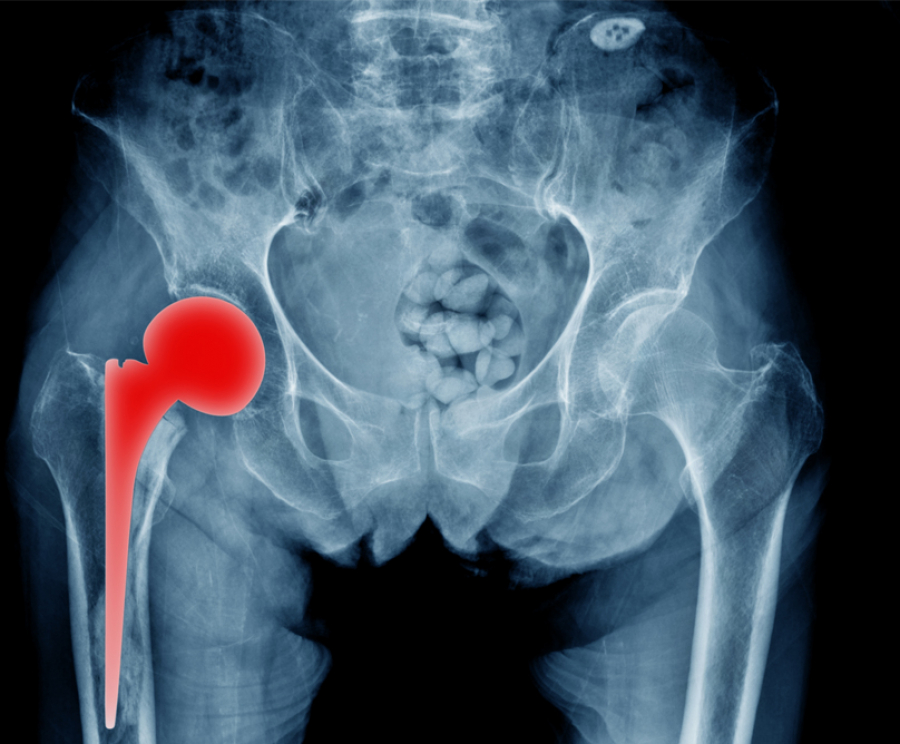

Ολική αρθροπλαστική ισχίου

Η ολική αρθροπλαστική του ισχίου βελτίωσε και συνεχίζει να βελτιώνει την ποιότητα ζωής εκατομμυρίων ασθενών εδώ και δεκαετίες. Ωστόσο, για μεγάλο χρονικό διάστημα παρέμενε μια βαριά, συχνά αιμορραγική επέμβαση που απαιτούσε μακρά νοσηλεία και αποκατάσταση. Στην πορεία των ετών η ορθοπαιδική χειρουργική εξελίχθηκε επιστημονικά και ταυτόχρονα εξελίχθηκε και η επιστήμη των υλικών που χρησιμοποιούνται στα χειρουργεία. Αποτέλεσμα αυτών των εξελίξεων αποτελούν οι νέες χειρουργικές τεχνικές που εντάσσονται στο χειρουργικό οπλοστάσιο του ορθοπαιδικού χειρουργού για την αντιμετώπιση της οστεοαρθρίτιδας του ισχίου.